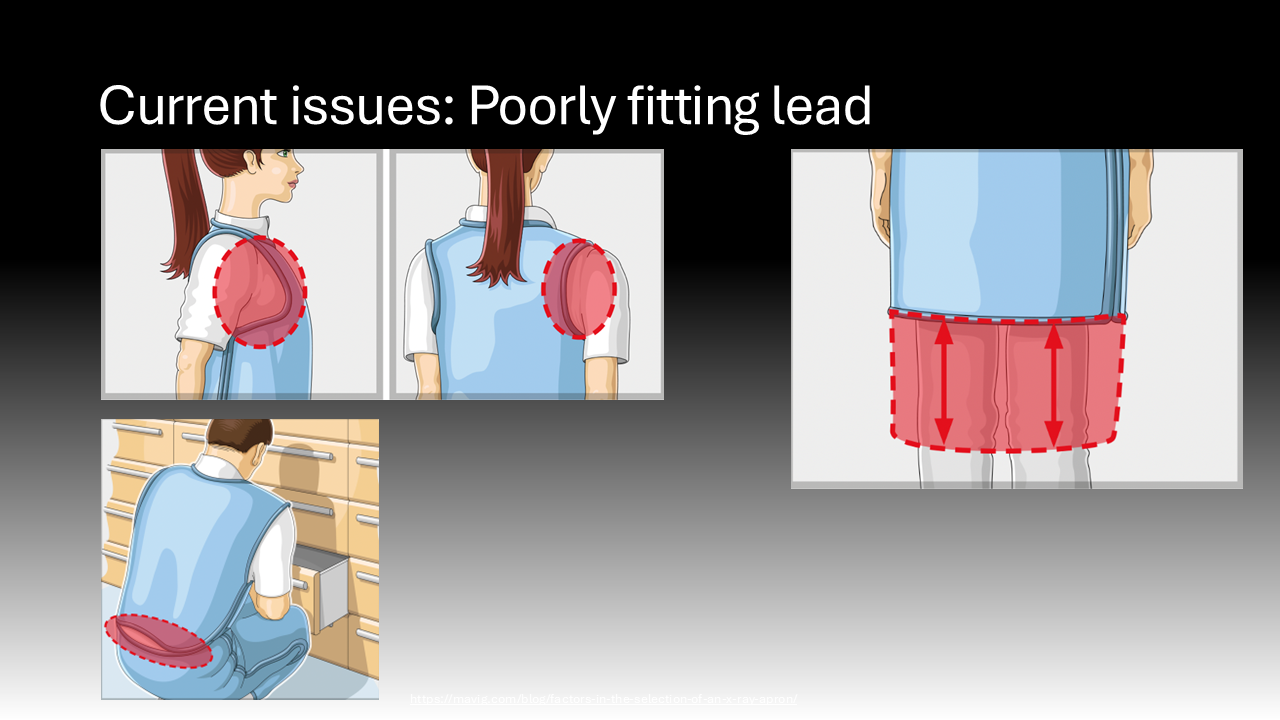

The major caveat to the efficacy of lead aprons is their fit. Many of the lead aprons historically have come in “unisex” sizing, tailored for men, leaving certain parts of women’s bodies poorly protected.4,13 This is particularly problematic in fully protecting the entirety of the breast tissue that is at high risk for malignancy.4,13 This may partly be mitigated for attending surgeons who are able to purchase their own lead or have their department purchase lead for them.4,13 However, trainees are often left scavenging for lead that fits poorly, placing them at unnecessarily high risk.10,13 It is critical to ensure that trainees have easy access to effective mitigation tools to ensure their health and wellness. Additionally, lead garments are heavy and cumbersome, which may discourage their use.